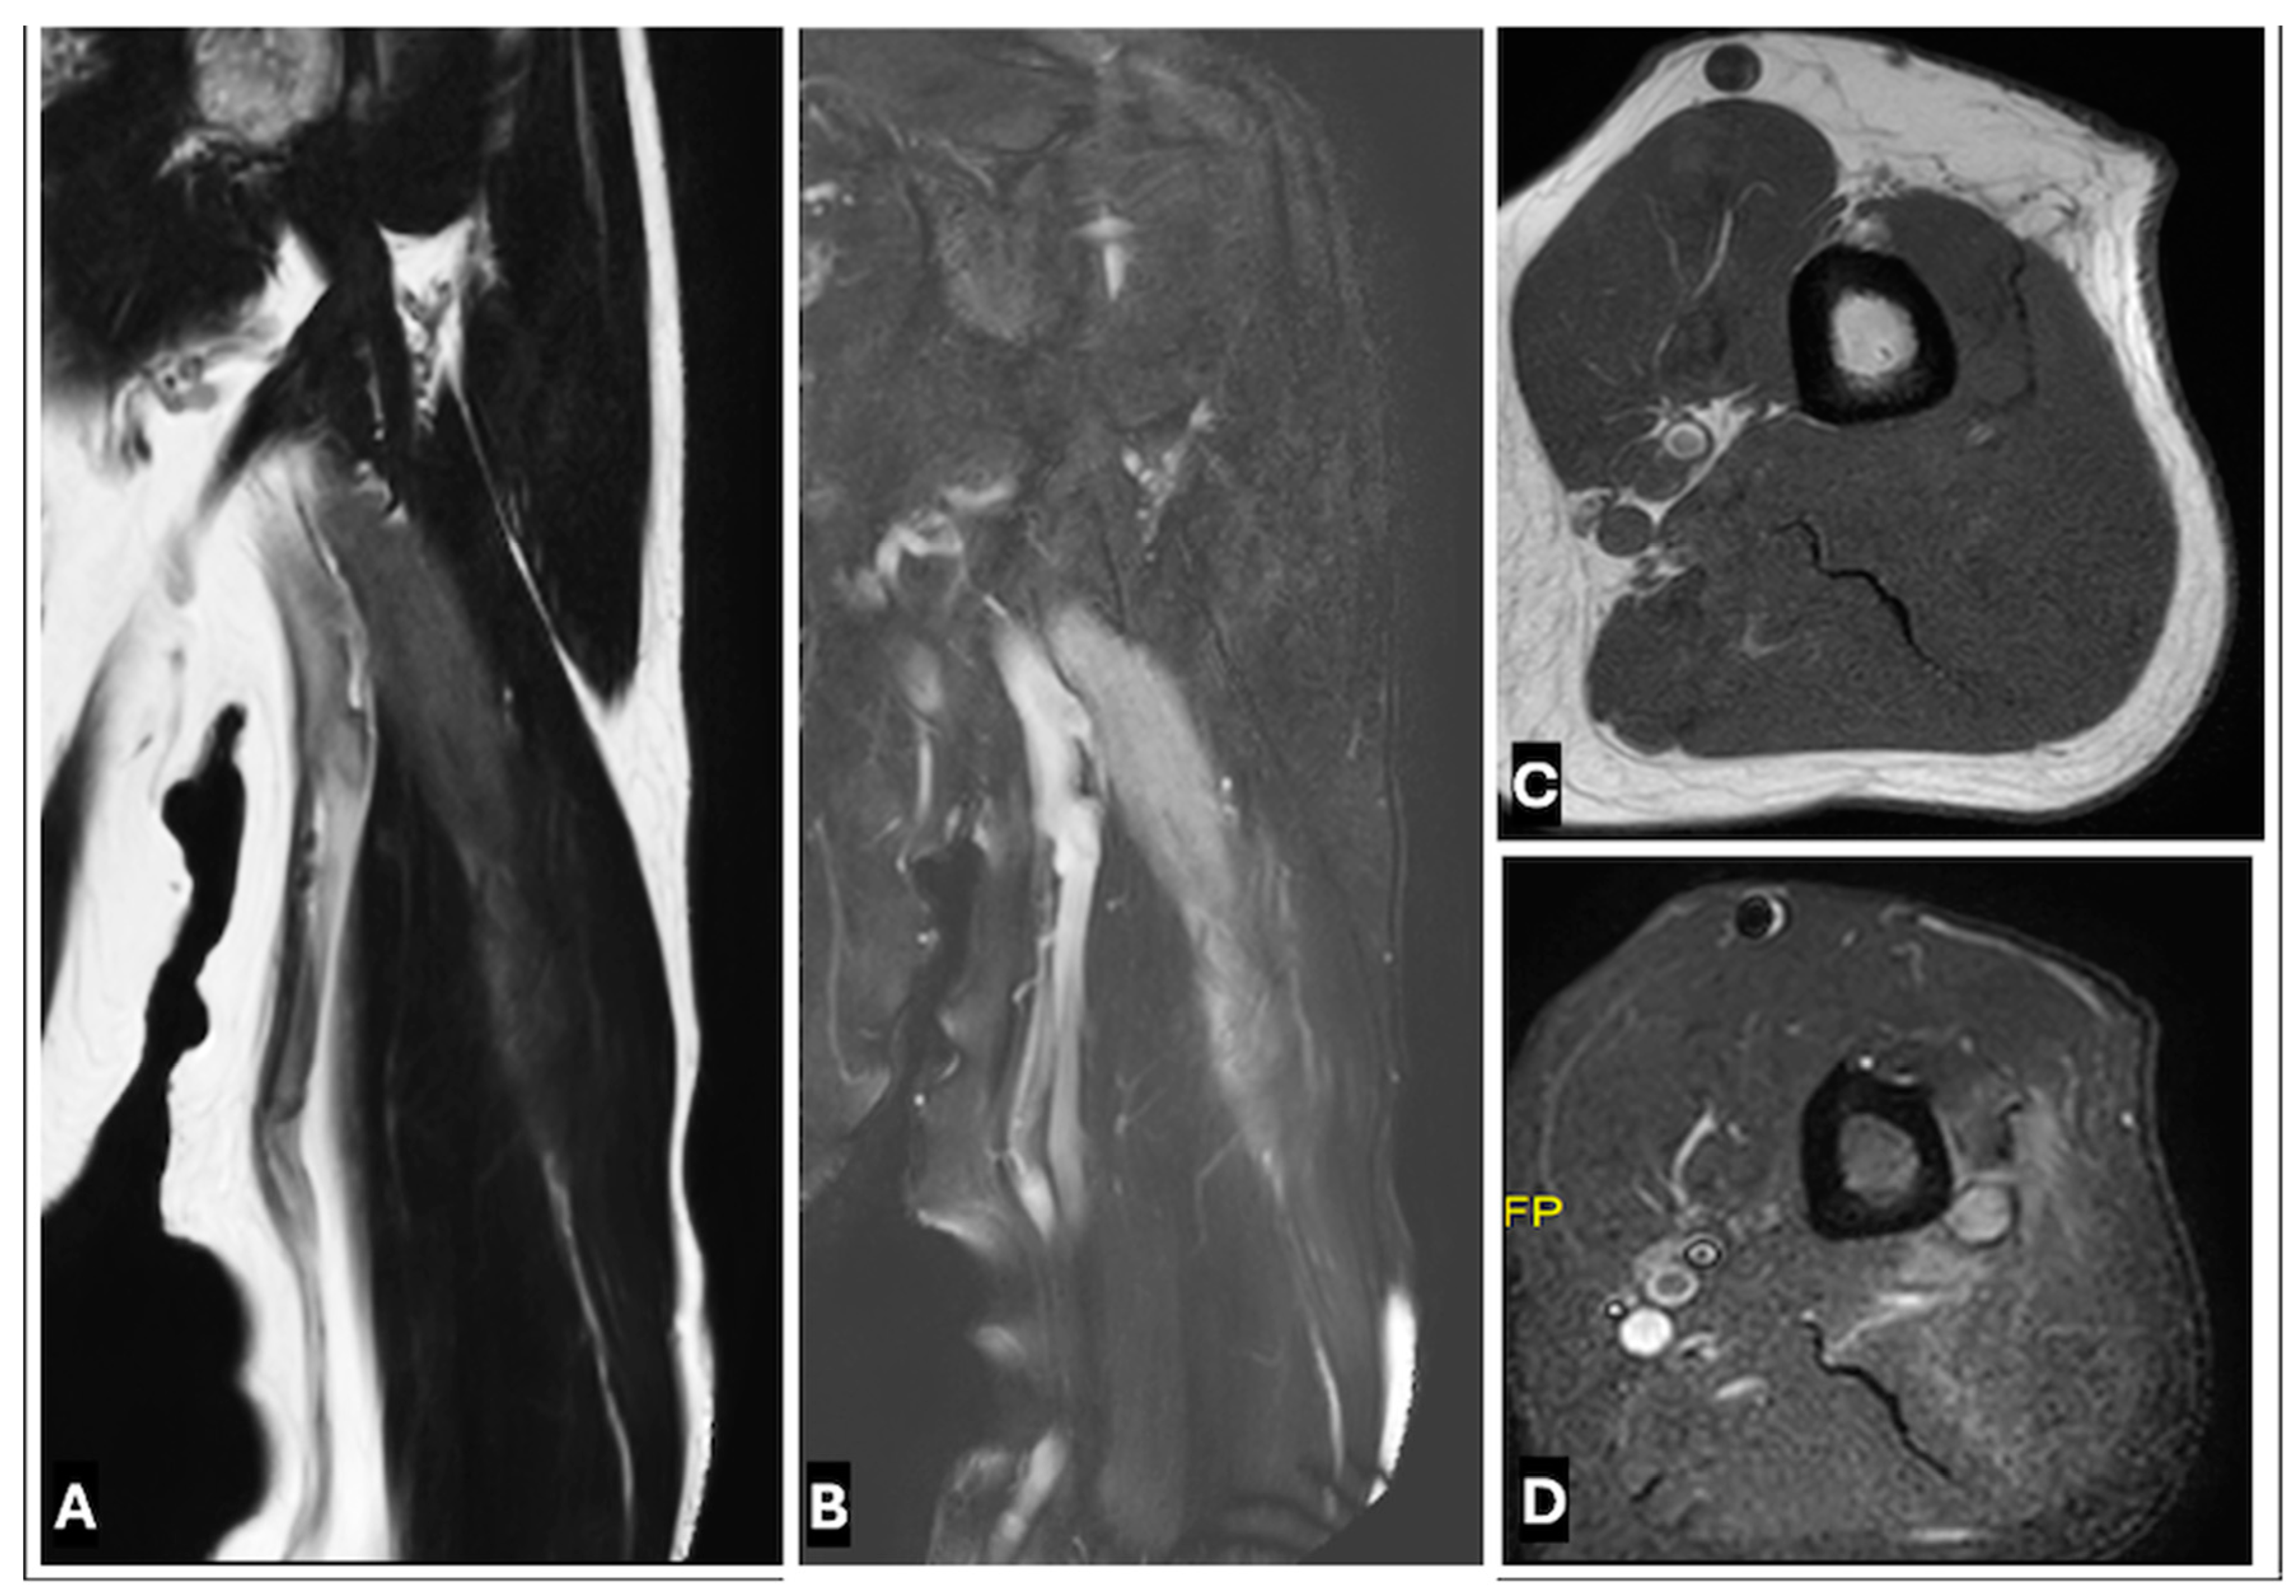

- Primary Sarcomas: Soft-tissue sarcomas are uncommon, accounting for just over 1% of adult malignancies. Synovial sarcoma, clear cell sarcoma, and epithelioid sarcomas are known to involve peripheral nerves. CT/MR reveals a large soft tissue mass with areas of necrosis or calcification and heterogeneous contrast enhancement. F-18 FDG uptake is useful for both tumor staging and treatment assessment (Figure 26, Figure 27 and Figure 28).